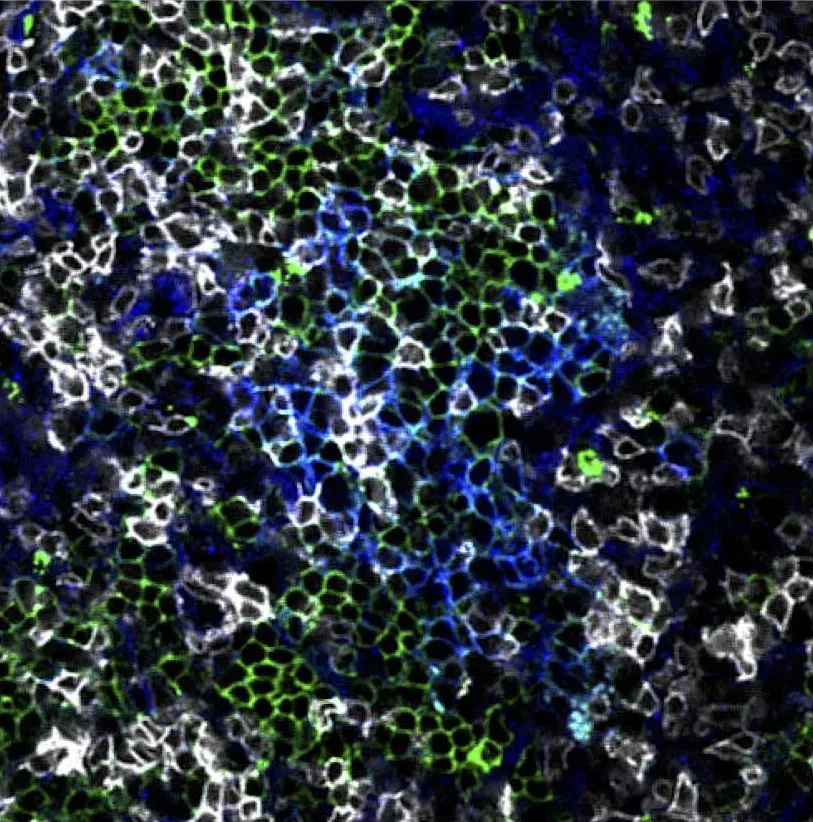

Image of lung tissue 14 days after IAV infection.

Image of lung tissue 14 days after influenza virus infection. Source: Denton et al. in Journal of Experimental Medicine.